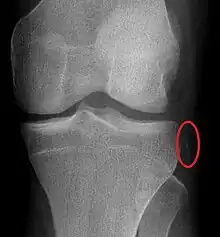

Plain X-rays, CT scan, ultrasonography, or MRI may help with the diagnosis.[2][11] Findings on X-ray that may be useful among those who have already reduced include a variable joint space, subluxation of the joint, or a Segond fracture.[5]

- ↑ Duprey K, Lin M (February 2010). "Posterior knee dislocation". The Western Journal of Emergency Medicine. 11 (1): 103–4. PMC 2850837. PMID 20411095.